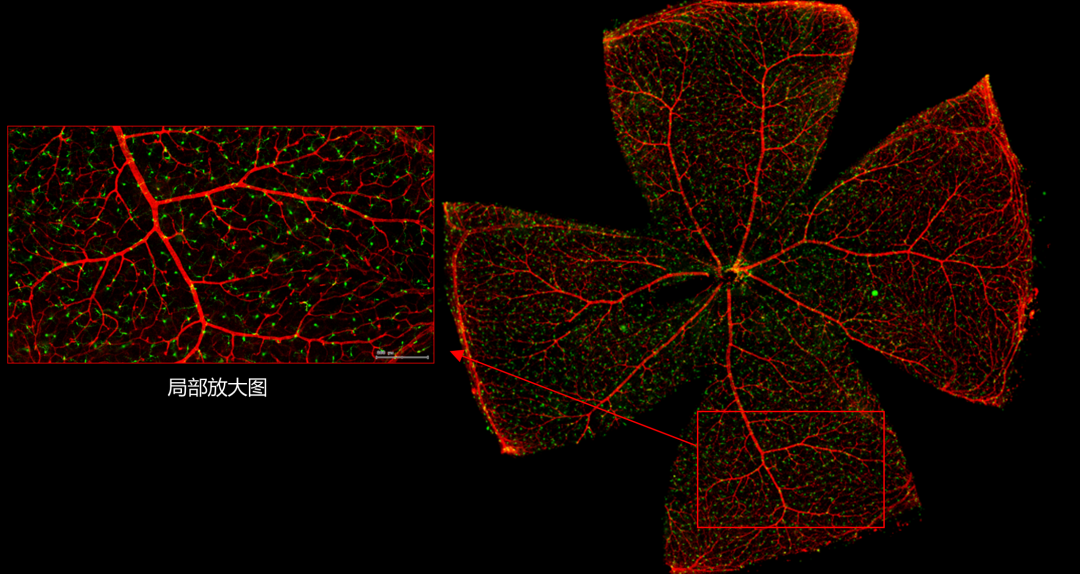

一般而言,眼底图像通常都是通过激光扫描成像进行采集,但是由于眼底可观测的视野往往是很有限的,一个患者的眼底信息需要多张扫描图像才能完全显示出来。这种局限性大大不利于病情进行全面的、细致的诊断。Tissue Cytometry全景组织流式定量分析技术进行全景图像获取,在单细胞、组织结构、细胞空间信息等多个层面进行定位、定性、定量分析。从而更好的对病变区域进行有针对性的跟踪观察和全面分析。

视网膜荧光样本中小胶质细胞胞体、神经纤维识别、血管识别、血管斑点识别、神经元与血管的距离分析。

1. 利用TissueFAXS系统进行玻片荧光的全景扫描。

2. 使用StrataQuest分析软件进行定量分析。

5. 识别血管的Texa Red染色区域面积及强度。

血管识别:根据Texa Red通道进行识别,并去除面积小的及非同一焦面的血管,仅对确定的清晰的同一焦面的大血管进行面积统计。

血管与小胶质细胞的距离0-0.1μm(红色框线标记)

血管与小胶质细胞的距离0.1-1μm(粉色标记)

血管与小胶质细胞的距离1-3μm(粉色标记)